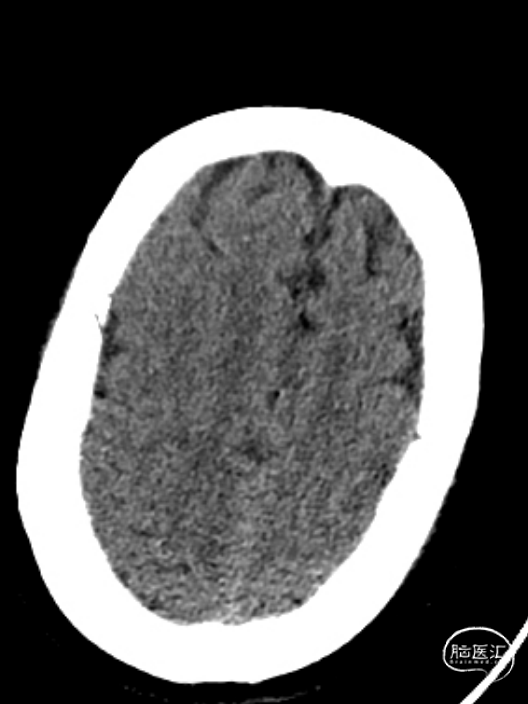

术前检查

患者为急性脑梗死,头颅CT未见明显低密度病灶,CTA提示:右侧颈内动脉及右侧大脑中动脉M1段闭塞,远端分支减少,显影浅淡。目前患者神经功能缺损严重,有急诊取栓手术指征。

术后第一天复查颅脑CT未见异常染色及大面低密度病灶。

查头颅MRI:右侧基底节区、右侧顶颞岛叶急性脑梗死。